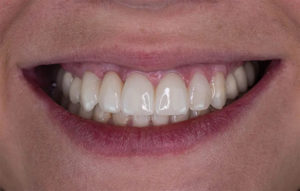

– велика естетичність, що особливо важливе для передніх зубів;

– збереження природного ясенного контуру;